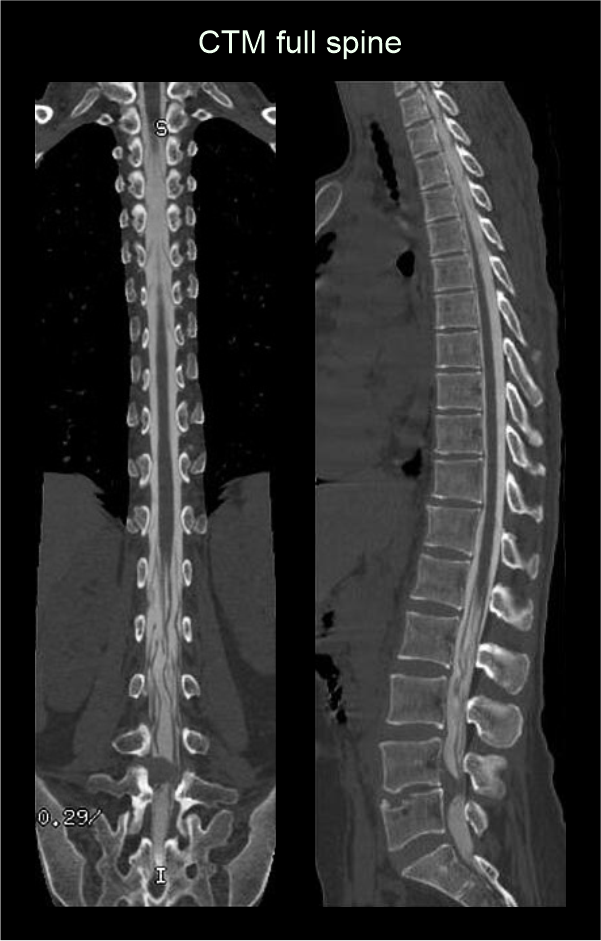

- Sagittal and coronal images with ≤ 2 mm slice thickness in bone window (WW: 3500, WL: 350).

- Contagious axial slices in bone window and soft-tissue window (WW:500, WL:50) with ≤ 2mm and ≤ 3mm slice thicknesses respectively.

- Axial images through inter-vertebral disk for the assessment of spinal cord compressions.